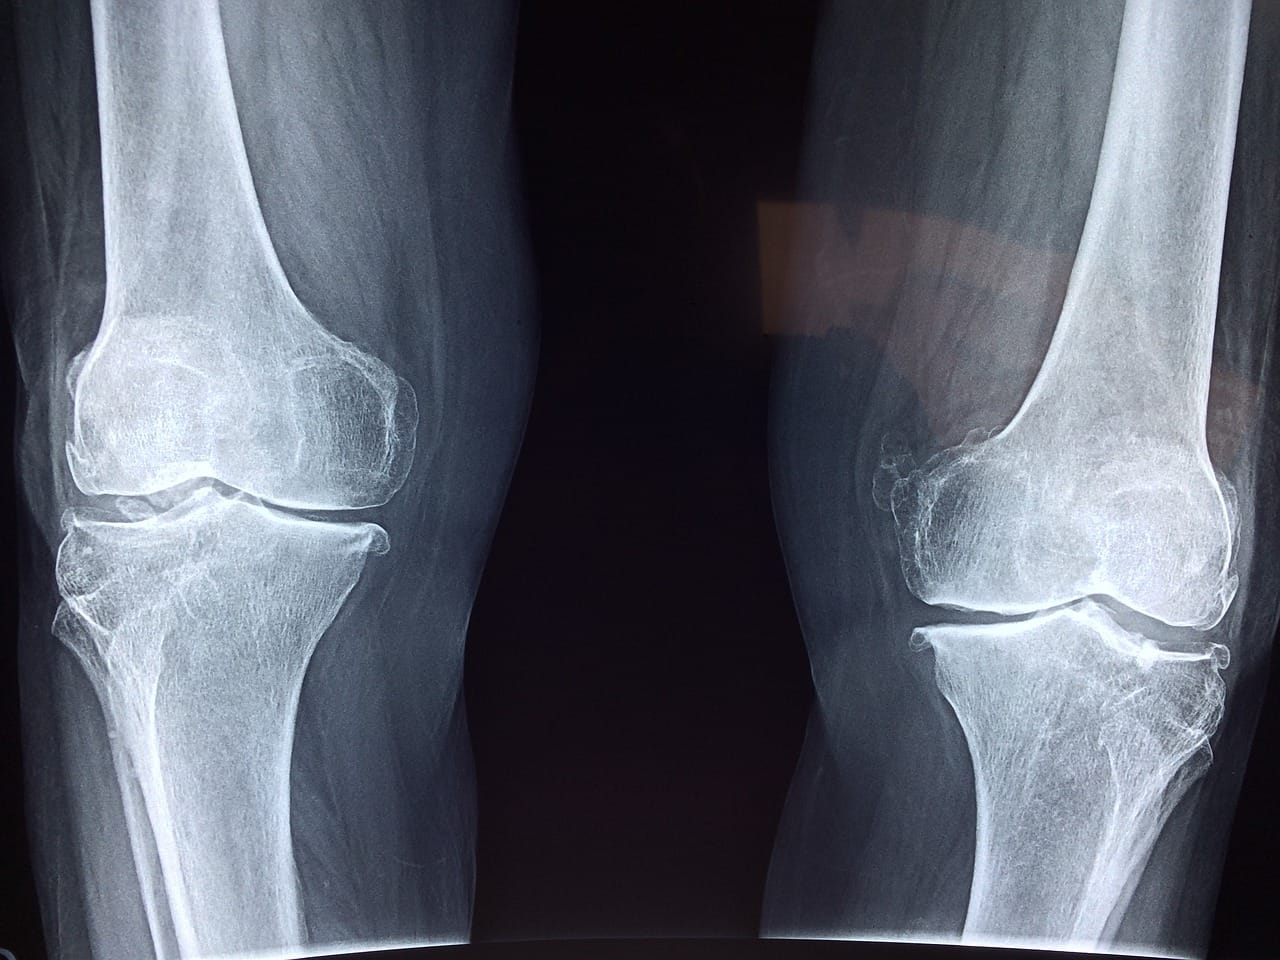

Building and maintaining bone mass is a big deal with 1 in 5 females and 1 in 20 men over the age of 50 showing signs of osteoporosis [1]. Bone mineral density seems to decline at a rate of 0.6% to 2.1% per year after the age of 60 without fighting gravity through resistance training [2]. According to the CDC, as high as 1 in 3 older adults will experience a fall each year, and over 1 in 3 of those falls will likely require medical attention. Currently, an estimated 300,000 hip fractures occur in the US each year which increases one’s risk of death for the subsequent year and one is never really out of the clear as this increased risk is seemingly still there 20 years after a fall [1].

It appears that resistance training may be able to increase bone mineral density (BMD) at a rate similar to pharmacological means [3, 4]. Furthermore, resistance training and medications may have an additive or even synergistic effect [5]. It appears that higher-intensity resistance training may be more effective for stimulating bone adaptations [6, 7].

The precision error for BMD measured via dual-energy X-ray absorptiometry (DEXA) can be close to the rate of increase or decline that one might see from annual aging or from the interventions listed above [8, 9]. Therefore, one would likely want to see an improvement beyond 1-2% to know that they overwhelmed the technical error of the device and operator. This metric could be tracked annually or every other year ideally utilizing the same positioning and scanning facility.